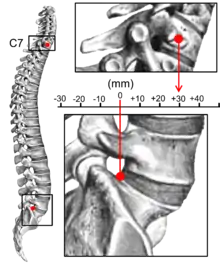

Kyphosis is an abnormally excessive convex curvature of the spine as it occurs in the thoracic and sacral regions.[1][2] Abnormal inward concave lordotic curving of the cervical and lumbar regions of the spine is called lordosis. It can result from degenerative disc disease; developmental abnormalities, most commonly Scheuermann's disease; Copenhagen disease, osteoporosis with compression fractures of the vertebra; multiple myeloma; or trauma. A normal thoracic spine extends from the 1st thoracic to the 12th thoracic vertebra and should have a slight kyphotic angle, ranging from 20° to 45°. When the "roundness" of the upper spine increases past 45° it is called kyphosis or "hyperkyphosis". Scheuermann's kyphosis is the most classic form of hyperkyphosis and is the result of wedged vertebrae that develop during adolescence. The cause is not currently known and the condition appears to be multifactorial and is seen more frequently in males than females.[3]